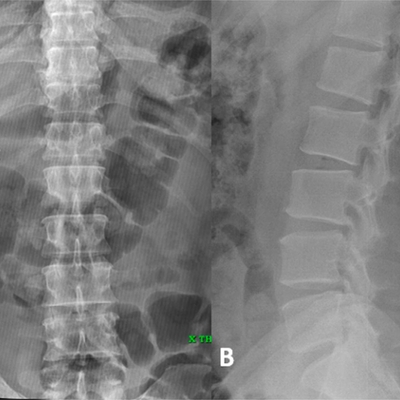

Click on an image below to view more info.